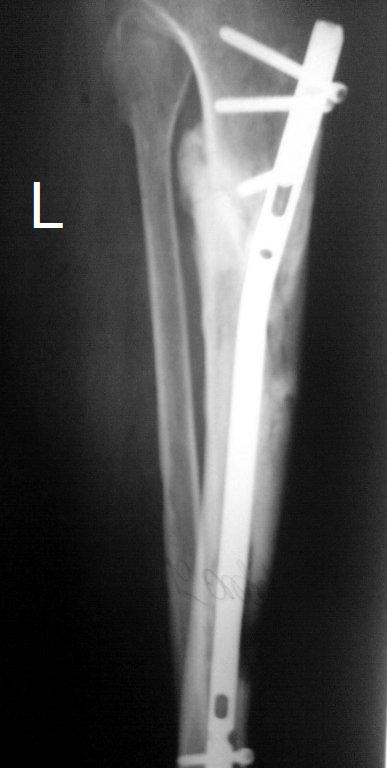

Итак, в настоящий момент больной пришел к нам с полной нагрузкой на оперированную конечность и с такой картиной

(см. приложение). Участок мягких тканей, с передней стенкой  нижней трети ББК, выгнил и представляет дефект

2×2,5 см. На перевязке - циркулярный(?) некроз костной трубки.

-----------   -----------

Вложение не в текстовом формате было извлечено…

Имя     : tibAP00.JPG

Тип     : image/jpeg

Размер  : 25574 байтов

Описание: отсутствует

Url     : http://weborto.net:8080/pipermail/ortho/attachments/20091123/dddb0a2c/attachment-0014.jpeg